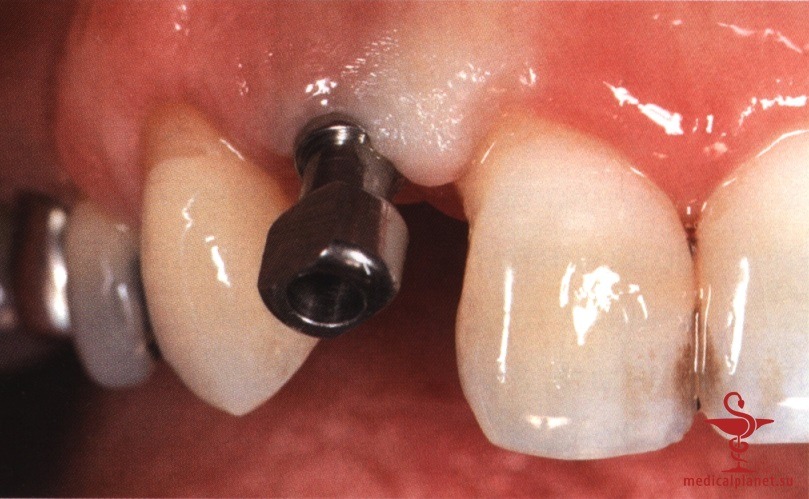

В качестве альтернативы можно провести пересадку субэпителиального соединительнотканного трансплантата (СТТ) для перекрывания лунки, избегая коронального смещения лоскута. Однако следует помнить, что выполнение нескольких хирургических манипуляций одновременно повышает риск нарушения кровоснабжения, от которого во многом зависит качество заживления. При этом часть СТТ остается открытой и заживает вторичным натяжением в течение относительно длительного периода.

Более того, происходит потеря объема трансплантата, а результат редко можно признать оптимальным, особенно в области десневых сосочков (рис. 2), поэтому в настоящее время такой протокол не рекомендуется.